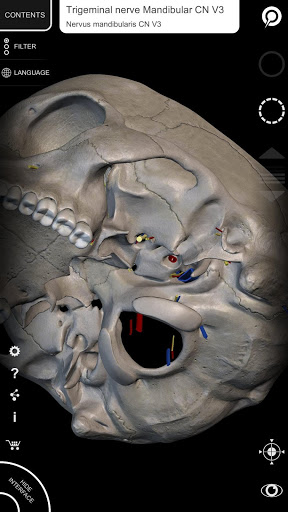

"Anatomy 3D Atlas" memungkinkan Anda mempelajari anatomi manusia dengan cara yang mudah dan interaktif.

Melalui antarmuka yang sederhana dan intuitif, Anda dapat mengamati setiap struktur anatomi dari sudut mana pun.

Model 3D anatomi sangat terperinci dan memiliki tekstur hingga resolusi 4k.

Pembagian berdasarkan wilayah dan tampilan yang telah ditetapkan sebelumnya memudahkan pengamatan dan studi bagian tunggal atau kelompok sistem dan hubungan antara organ yang berbeda.

MODEL ANATOMI 3D

saraf • Sistem pernapasan • Sistem pencernaan • Sistem urogenital (pria dan wanita) • Sistem endokrin • Sistem limfatik • Sistem mata dan telinga FITUR • Antarmuka yang sederhana dan intuitif • Putar dan perbesar setiap model dalam ruang 3D • Opsi untuk menyembunyikan atau mengisolasi satu atau beberapa model yang dipilih • Filter untuk menyembunyikan atau menampilkan setiap sistem • Fungsi pencarian untuk menemukan setiap bagian anatomi dengan mudah • Fungsi penanda untuk menyimpan tampilan khusus • Rotasi cerdas yang menggerakkan pusat rotasi secara otomatis • Fungsi transparansi • Visualisasi otot melalui tingkat lapisan dari yang superfisial hingga yang terdalam • Dengan memilih model atau pin, istilah anatomi terkait akan muncul • Deskripsi otot: asal, • Tampilkan/ Sembunyikan antarmuka UI (sangat berguna dengan layar kecil) MULTIBAHASA • Istilah anatomi dan antarmuka pengguna tersedia dalam 11 bahasa: Latin, Inggris, Prancis, Jerman, Italia, Portugis, Turki, Rusia, Spanyol, Mandarin, Jepang, dan Korea • Istilah anatomi dapat ditampilkan dalam dua bahasa secara bersamaan PERSYARATAN SISTEM • Android 8.0 atau yang lebih baru, perangkat dengan RAM minimal 3GB Reversi

• Sistem saraf